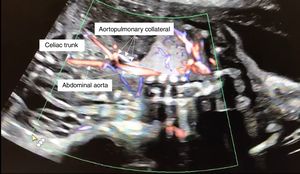

A 20-year-old primigravida was referred to the fetal cardiology clinic at 22 weeks’ gestation due to an intrapulmonary mass suggestive of pulmonary sequestration. The fetal echocardiogram showed a structurally normal heart and a tortuous feeding vessel arising from the abdominal aorta, proximally to the celiac trunk (Figure 1). She maintained regular follow-up, during which time the intrapulmonary mass gradually decreased in size and the collateral artery disappeared.